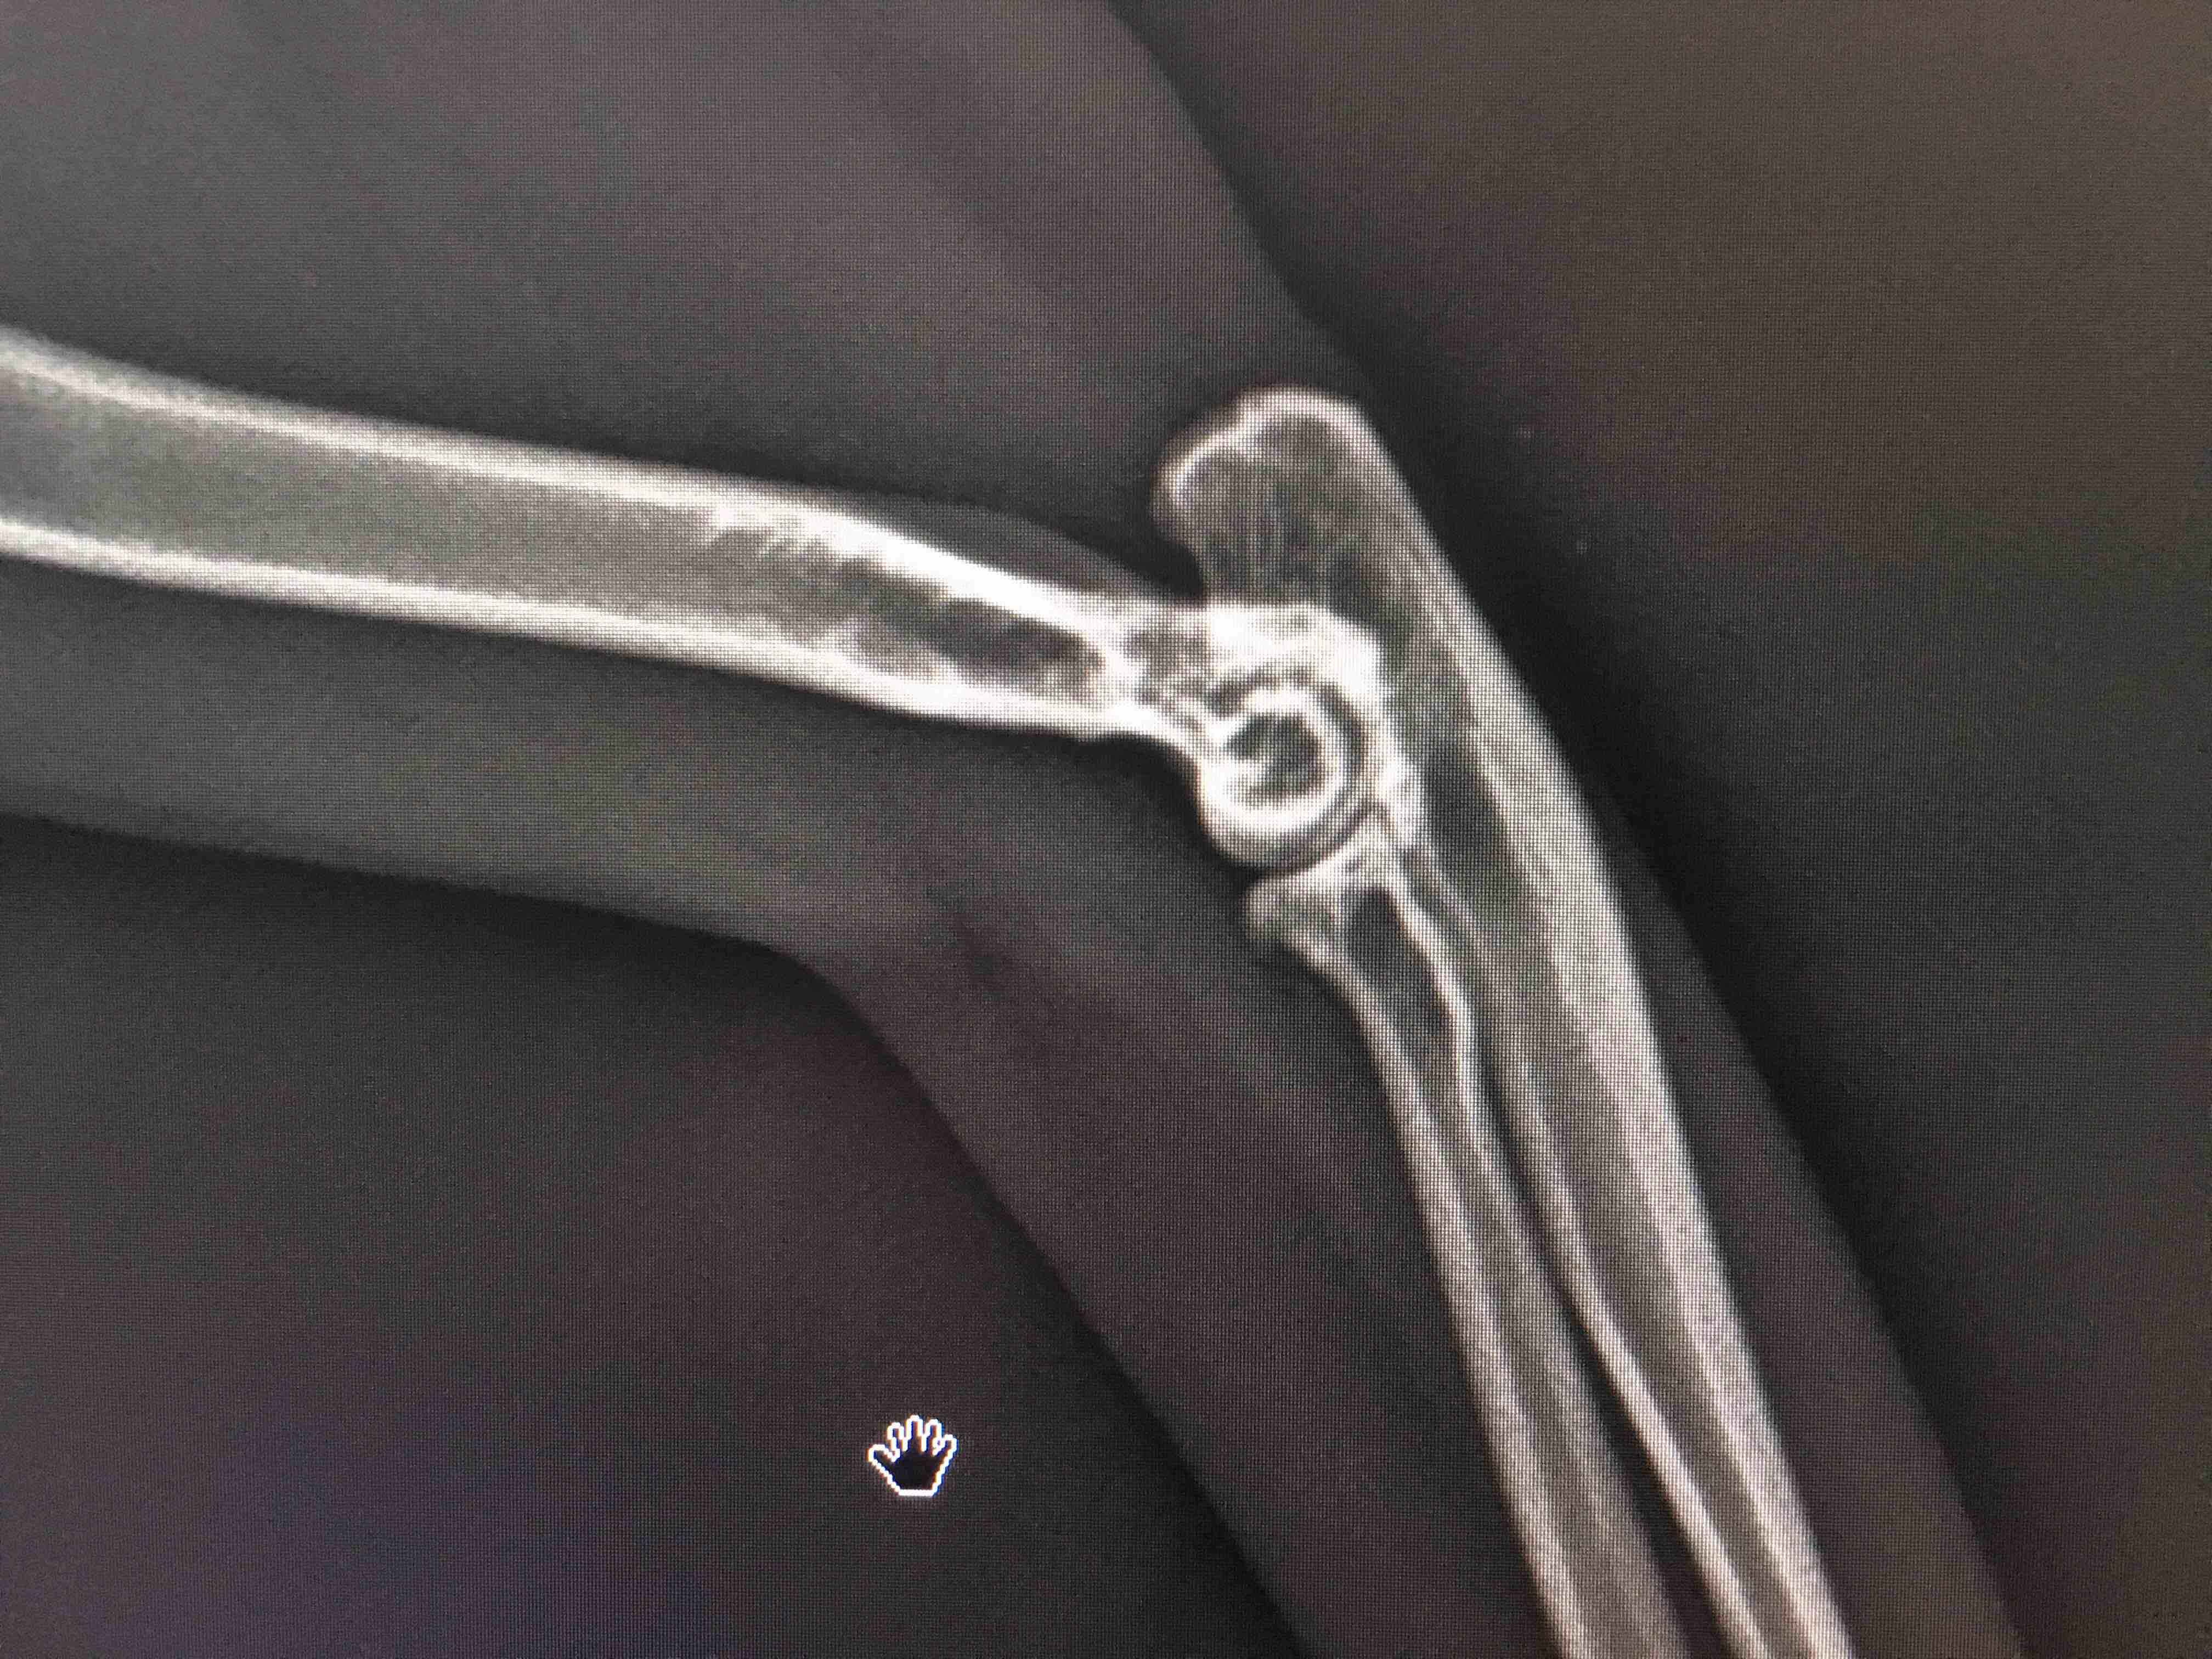

What is wrong with my 3 years old cat’s right leg.When she wake up she prefer not to use her right leg for few seconds then she stretches and she starts the use it.She eats fine,she can run and she can play.

Hi there and thank you for using Petco Pet Education Center, formerly Petcoach to address your concern. Based on the x-rays, I do not see any immediate concerning changes. However, on the right leg where the elbow is, it appears that there may be an increased density (bone sclerosis) of what we call the cortical bone. This may indicate early disease or something is beginning to affect the bone. I would recommend providing adequate rest for her for the next 4 weeks as well as give an anti-inflammatory to reduce any inflammation / pain she may be experiencing. I would recheck the x-rays in 4 weeks to see if there has been any change with the bone. I hope this helps! Please let me know if you have any other questions or concerns and I would be more than happy to help you further!